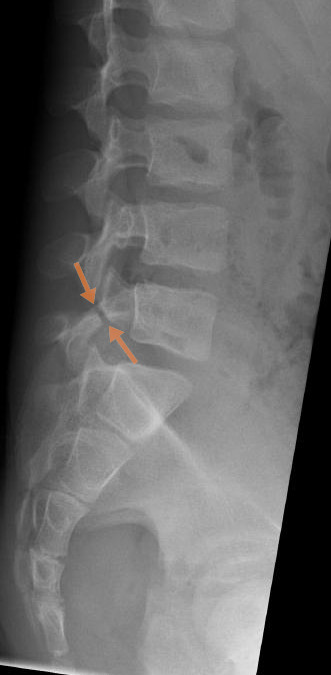

spondylolysis (lumbar)

separation of pars interarticularis (neck), most common at L4-5